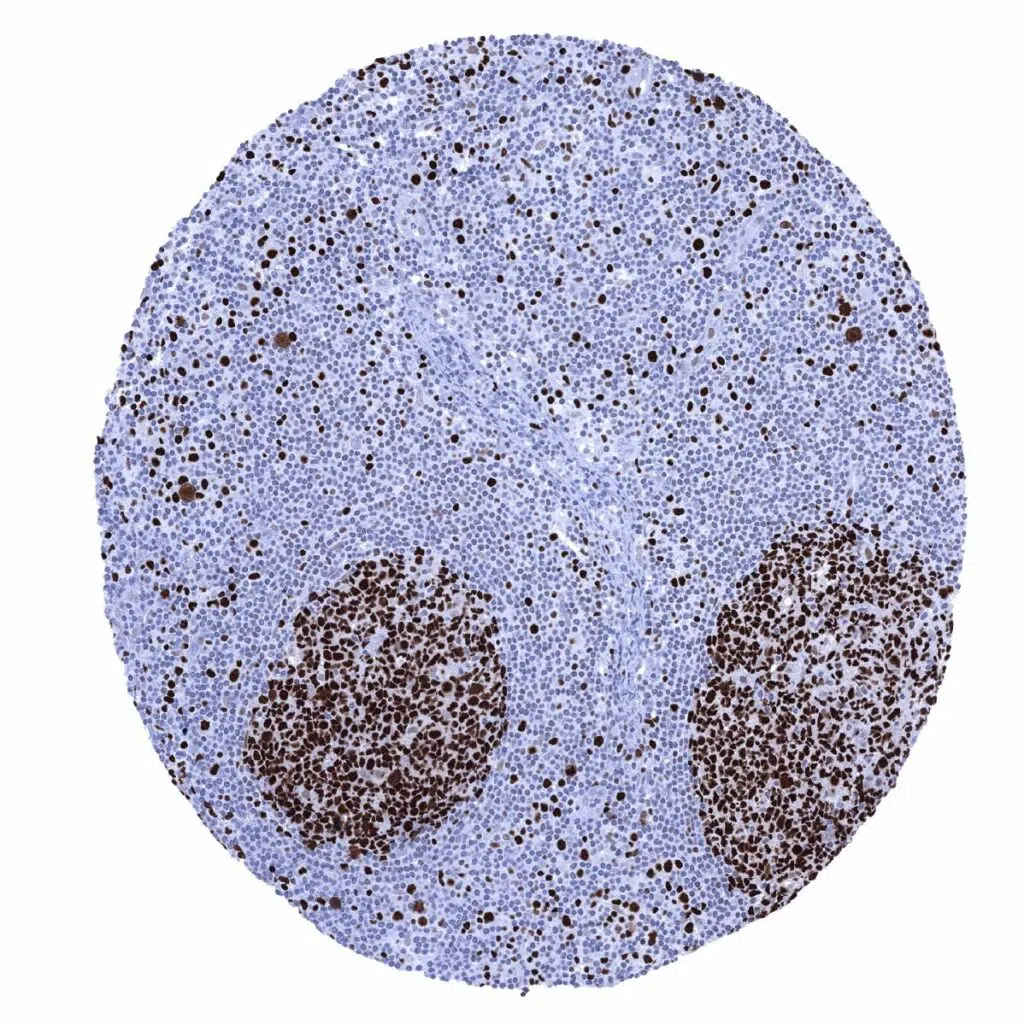

Lymph node – Many lymphocytes are MCM7 positive. A particularly strong MCM7 staining occurs in most cells of germinal centres and in scattered individual cells of the interfollicular zone